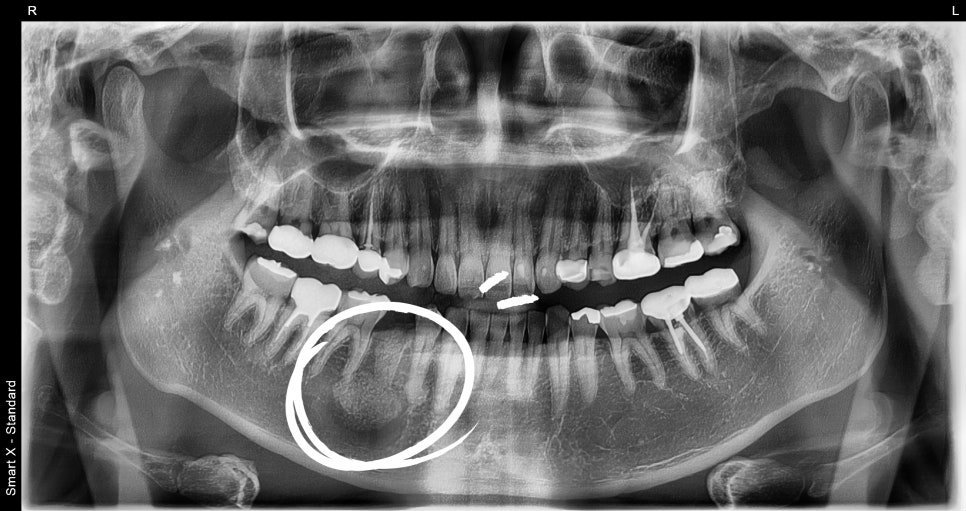

As a result of panoramic imaging and CBCT (3D CT) examination,

a well-defined radiolucent lesion was identified within the mandible in that area.

Diagnostic result: suspected benign tumor-like lesion within the mandible. The lesion was a circular cystic lesion about 2.5 cm in size, and unlike inflammation, it was a well-demarcated lesion distinguishable from the surrounding tissue.

Comparison before and after treatment

Postoperative management and results

✔️ Minimal bleeding immediately after surgery, stable recovery without complications

✔️ At suture removal after 1 week, pain and swelling were both controllable

✔️ Pathology result: Odontogenic cyst / benign tumor-like lesion

✔️ Currently being followed up with the tooth preserved